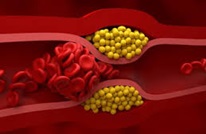

As detailed in a recent paper published in the journal Science Advances, first spotted by The Guardian, the project made an alarming discovery: some of the pieces of plastic were becoming stuck, causing more chunks to accumulate behind them in what one of the researchers likened to a “car crash.”

When encountering tight bends within the organs’ cortex vessels, the tiny pieces of polystyrene appear to have gotten absorbed by immune cells, creating unusually-shaped cells that then become stuck.

Some of these blockages became unstuck by themselves over time. However, the finding that stuck pieces of microplastics can get lodged in the first place and reduce blood flow is concerning.

“Environment microplastics might be another important risk factor for cardiovascular disease and received scant attention so far,” the researchers wrote. “Our findings provide a mechanistic explanation for tissue damage induced by microplastics, particularly regarding their effects on vascular obstruction.”

“Environment microplastics might be another important risk factor for cardiovascular disease and received scant attention so far,” the researchers wrote. “Our findings provide a mechanistic explanation for tissue damage induced by microplastics, particularly regarding their effects on vascular obstruction.”

But as the authors note, it’s important to point out that we still don’t know if the same blockages would take place in the human brain as well, as our vessels tend to be much larger.

“Moreover, humans are exposed to a variety of [microplastic] sizes, and the combinatorial effects of different [microplastic] sizes on the likelihood of inducing infarctions remain to be estimated,” they wrote in their paper. “The use of larger mammals or animal models that more closely resemble the human circulatory system, such as nonhuman primates, is thus crucial for studying this process.”